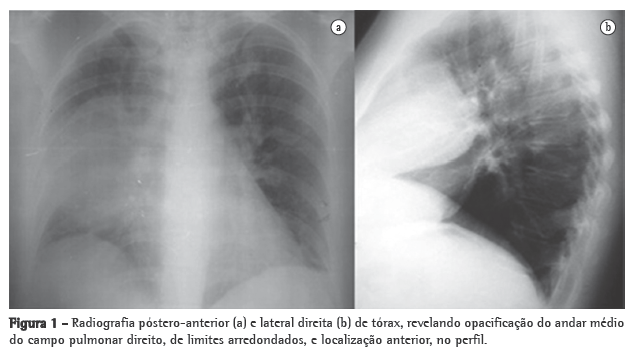

Apresentava também hipoxemia ao ar ambiente (PaO2: 79,5 mmHg) e ligeira hipocapnia (33 mmHg). A radiografia do tórax revelou uma opacidade no terço médio do campo pulmonar direito (Figura 1).

A radiografia do tórax foi repetida no 8º dia de internamento, mostrando persistência da opacidade já descrita. Para um melhor esclarecimento realizou-se, então, uma TC torácica, que revelou uma formação sólida, no mediastino anterior, com 10 cm no maior diâmetro, com planos de clivagem com o coração e o pulmão, insinuando-se entre os lobos pulmonares e comprimindo-os. Realizou-se também uma ressonância magnética para um melhor esclarecimento dos limites da lesão, nomeadamente no que se refere ao plano de clivagem com as estruturas do mediastino (Figura 2), que confirmou as imagens da TC.